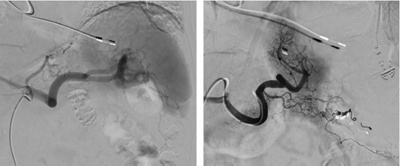

In Lokalanästhesie wird – vergleichbar mit einer Herzkatheteruntersuchung – ein Katheter in der Leistenarterie eingeführt und unter Röntgen-Kontrolle zur Milzarterie navigiert. Je nach zugrundeliegender Ursache kann dann mit verschiedenen Embolisationsmaterialien endovaskulär die Milzarterie mit Metallspiralen (Coils) oder Gefässkorken (Vascular Plug) verschlossen, es kann aber auch eine Verödung des Milzgewebes mittels Mikrokügelchen durchgeführt werden.

Gefässdarstellung der Milz vor (A) und nach (B) subtotaler Verödung (Embolisation) des Milzgewebes mittels Mikrokügelchen (Partikeln) bei einem Patienten mit therapierefraktärem M. Werlhof (Immunthrombozytopenie, ITP).